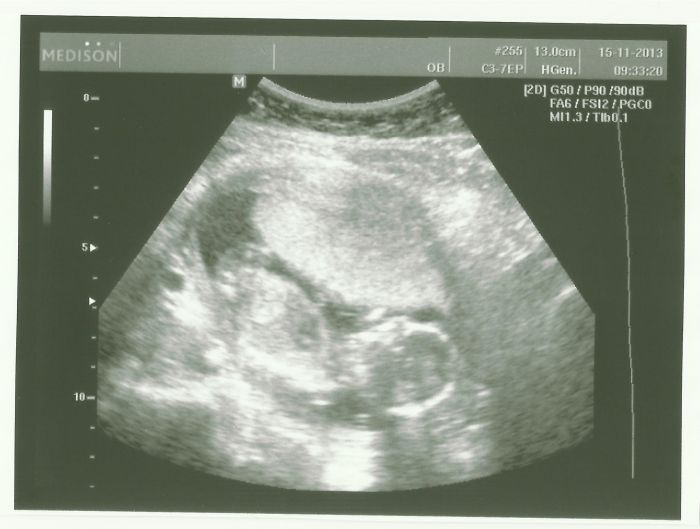

Tak jsem zpátky z kontroly a ultrazvuku :) Konečně jsem zase klidná, že je všechno tak, jak to být má

Škoda jen, že nemá pí doktorka lepší ultrazvuk, co to bude ještě nevíme. Dneska začínáme 16. týden (14+6) a naše malé bude asi akrobat, předvedl stoj na hlavě a něco jako svíčku

Má se čile k světu, huráááá. Nahraju nové fotečky až bude čas.

[389862] Jé, to je hezký, jak ho máš na těch snímcích po částech

[389976] když ono je to takové hrozně živé a neposedné mimino

Ani chvíli se nezastavilo, takže takhle po částech jsme ho stačili zachytit. Ale ten zadek s nožkama je prostě best